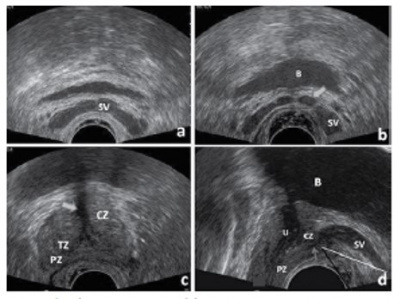

4. Suprapubic ultrasonography

환자에게 불편을 주지 않고 전립선의 무게를 측정할 수 있는 장점이 있으나, 치골에 의하여 초음파가 차단되기 때문에 전체적인 초음파 영상을 얻을 수 없는 단점이 있다.